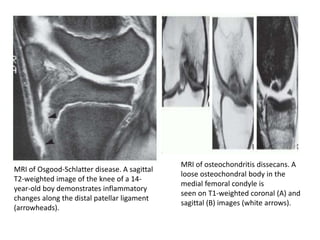

MRI of Osgood-Schlatter disease. A sagittal

T2-weighted image of the knee of a 14-

year-old boy demonstrates inflammatory

changes along the distal patellar ligament

(arrowheads).

MRI of osteochondritis dissecans. A

loose osteochondral body in the

medial femoral condyle is

seen on T1-weighted coronal (A) and

sagittal (B) images (white arrows).